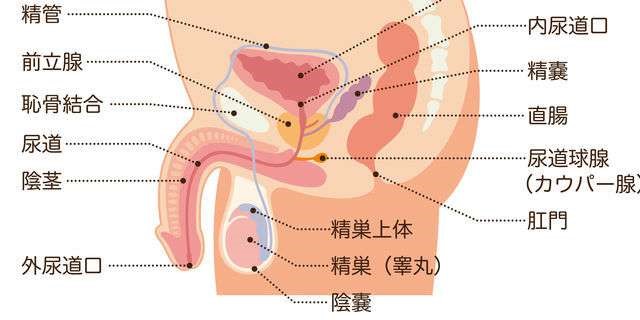

前立腺炎の場合、一般的には会陰部(肛門の前)の鈍痛、 睾丸の鈍痛、排尿痛があげられます。 そして、前立腺炎では多くの場合、この会陰部に痛みが生じます。 会陰部の痛み 急性前立腺炎の場合 急性前立腺炎の場合は、高熱と会陰部痛をともなうため、 男性 会陰部にしこり person 30代/男性 前も相談させて頂きました。 だんなが睾丸のすぐ下から肛門の間にしこりを発見しました。 去年には肛門周囲膿瘍で入院したこともあり、診察を受けに行きましたが、経過は大丈夫で、しこりについては1919 男性 男性の尿道は長く、外尿道口から入った細菌は、膀胱に達する前に排尿によって流されることが多い。前立腺からの分泌液には、細菌の侵入を防ぐ働きがある。 女性 女性は、男性に比べて、尿道が短い上、肛門や膣前庭部と外尿道口が近いので、その分、細菌が膀胱の中に入りやすい。

会陰 ( えいん )とは、 解剖学 において、狭義では 外陰部 と 肛門 の間、広義では左右の 大腿 と 臀部 で囲まれる 骨盤 の出口全体をさす。 恥骨結合 と左右の 坐骨結節 、 尾骨 を結ぶ菱形部となる。会陰と残尿感の解消には、 一体どのような関係性があるのでしょうか。 男性は蟻の門渡りを押すことで残尿感を解消できるのか? 排尿を終えた直後なのに「まだ膀胱内に尿が残っているような気がする、 なんだかスッキリしない」という不快感を覚える 男性の陰部のかゆみの原因として考えられる疾患とは? 男性の陰部にかゆみの症状があるとき、大まかな原因としては「性感染症」「皮膚疾患」の2つの場合が考えられます。 かゆみのある性感染症としては「性器ヘルペス・尖圭コンジローマ・梅毒」などがあり、どれも性行為により感染する可能性があります。 性器ヘルペスでは、陰部に水膨れができ

会陰部 広義の会陰の定義 (会陰部も参照) 前方の陰丘、外側の大腿内側面、後方の殿溝と殿間裂の上縁に挟まれた菱形の領域 (M) 狭義の会陰の定義 男性の場合尿道と会陰の間、女性の場合膣と肛門の間を指す (KH237) WordNet the general region between the anus and the男性の会陰は前後径5~6センチメートル、女性では2~3センチメートルである。 この部分の皮膚の正中線には色素に富んだ会陰縫線 (ほうせん)があり、男性では陰嚢縫線に続く。 会陰部皮下には脂肪組織、平滑筋線維が多く存在し、その深部には横紋筋からなる会陰筋層がある。 骨盤腔 (こう)を上方からみると、骨盤下口を会陰筋が筋膜、腱膜 (けんまく)とともに会陰部のヘルニアについて情報をまとめました。 ヘルニア治療辞典 男性と女性では、起こる場所が異なると言われていますが、女性の方がかかる率が高くなっています。 恐らく、女性は妊娠や出産などがあるため、会陰部が大きく収縮することが原因の1つではないかと考えられます。

生殖器の構造 看護roo カンゴルー

男性の生殖器系の構造 21 男性の健康上の問題 Msdマニュアル家庭版